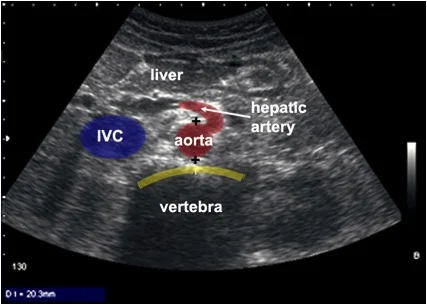

- Identify normal chest and abdominal anatomy

- Patient anatomy

The RUQ should be divided into 3 zones.

1. Above/Below the diaphragm,

2. Morrison’s pouch (hepato-renal recess)

3. Para-colic gutter: Around the inferior hepatic edge/inferior pole of kidney

The key is to know your landmarks, and STOP, STAY and widely FAN through each zone well, adjusting your depth as necessary to keep the area of interest centered on your screen.

Start high to stay and fan (anterior to posterior) around the diaphragm. Then, SLIDE down into another rib space, stop, stay and fan around the entire kidney. An additional rib space may be necessary to evaluate the para-colic gutter.